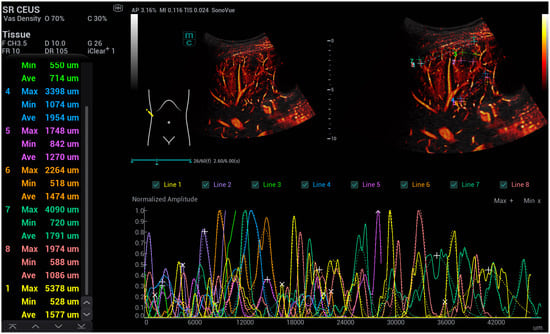

- Kaiser, U.; Vehling-Kaiser, U.; Kück, F.; Gilanschah, M.; Jung, F.; Jung, E.M. Super-Resolution contrast-enhanced ultrasound examination down to the microvasculature enables quantitative analysis of liver lesions: First Results. Life 2025, 15, 991. [Google Scholar] [CrossRef]

| Osler’s Disease | No Osler’s Disease | p-Value | |

|---|---|---|---|

| N = patient | n = 10 | n= 20 | |

| N = number of measurements | n = 30 | n = 60 | |

| diameter: close to the capsule | 5133.7 ± 1456.6 | 1972.3 + 399.2 | 6.18989 × 10−13 |

| diameter: at the level of the portal vein | 2175.3 ± 417.5 | 2890.7 + 606.9 | 3.00779 × 10−11 |

| area: close to the capsule | 68.9 ± 8.8 | 8.9 + 1.99 | 1.4051 × 10−26 |

| area: at the level of the portal vein | 35.8 ± 7.73 | 16.8 + 3.66 | 8.29298 × 10−15 |